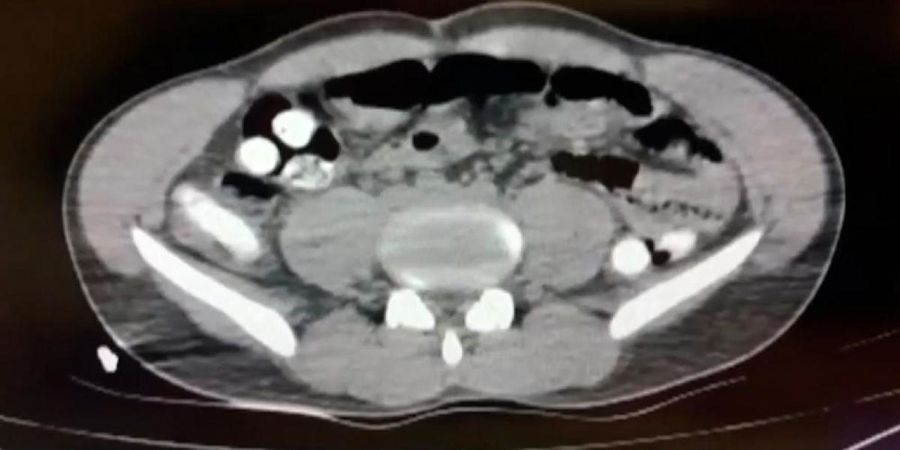

یک مسافر ایرانی در شهر آغری ترکیه به اتهام حمل مواد مخدر دستگیر شد. مهران یک کیلو و ۱۲۶ گرم مواد مخدر شامل تریاک را با قورت دادن کپسول‌ها در معده خود حمل می‌کرد.